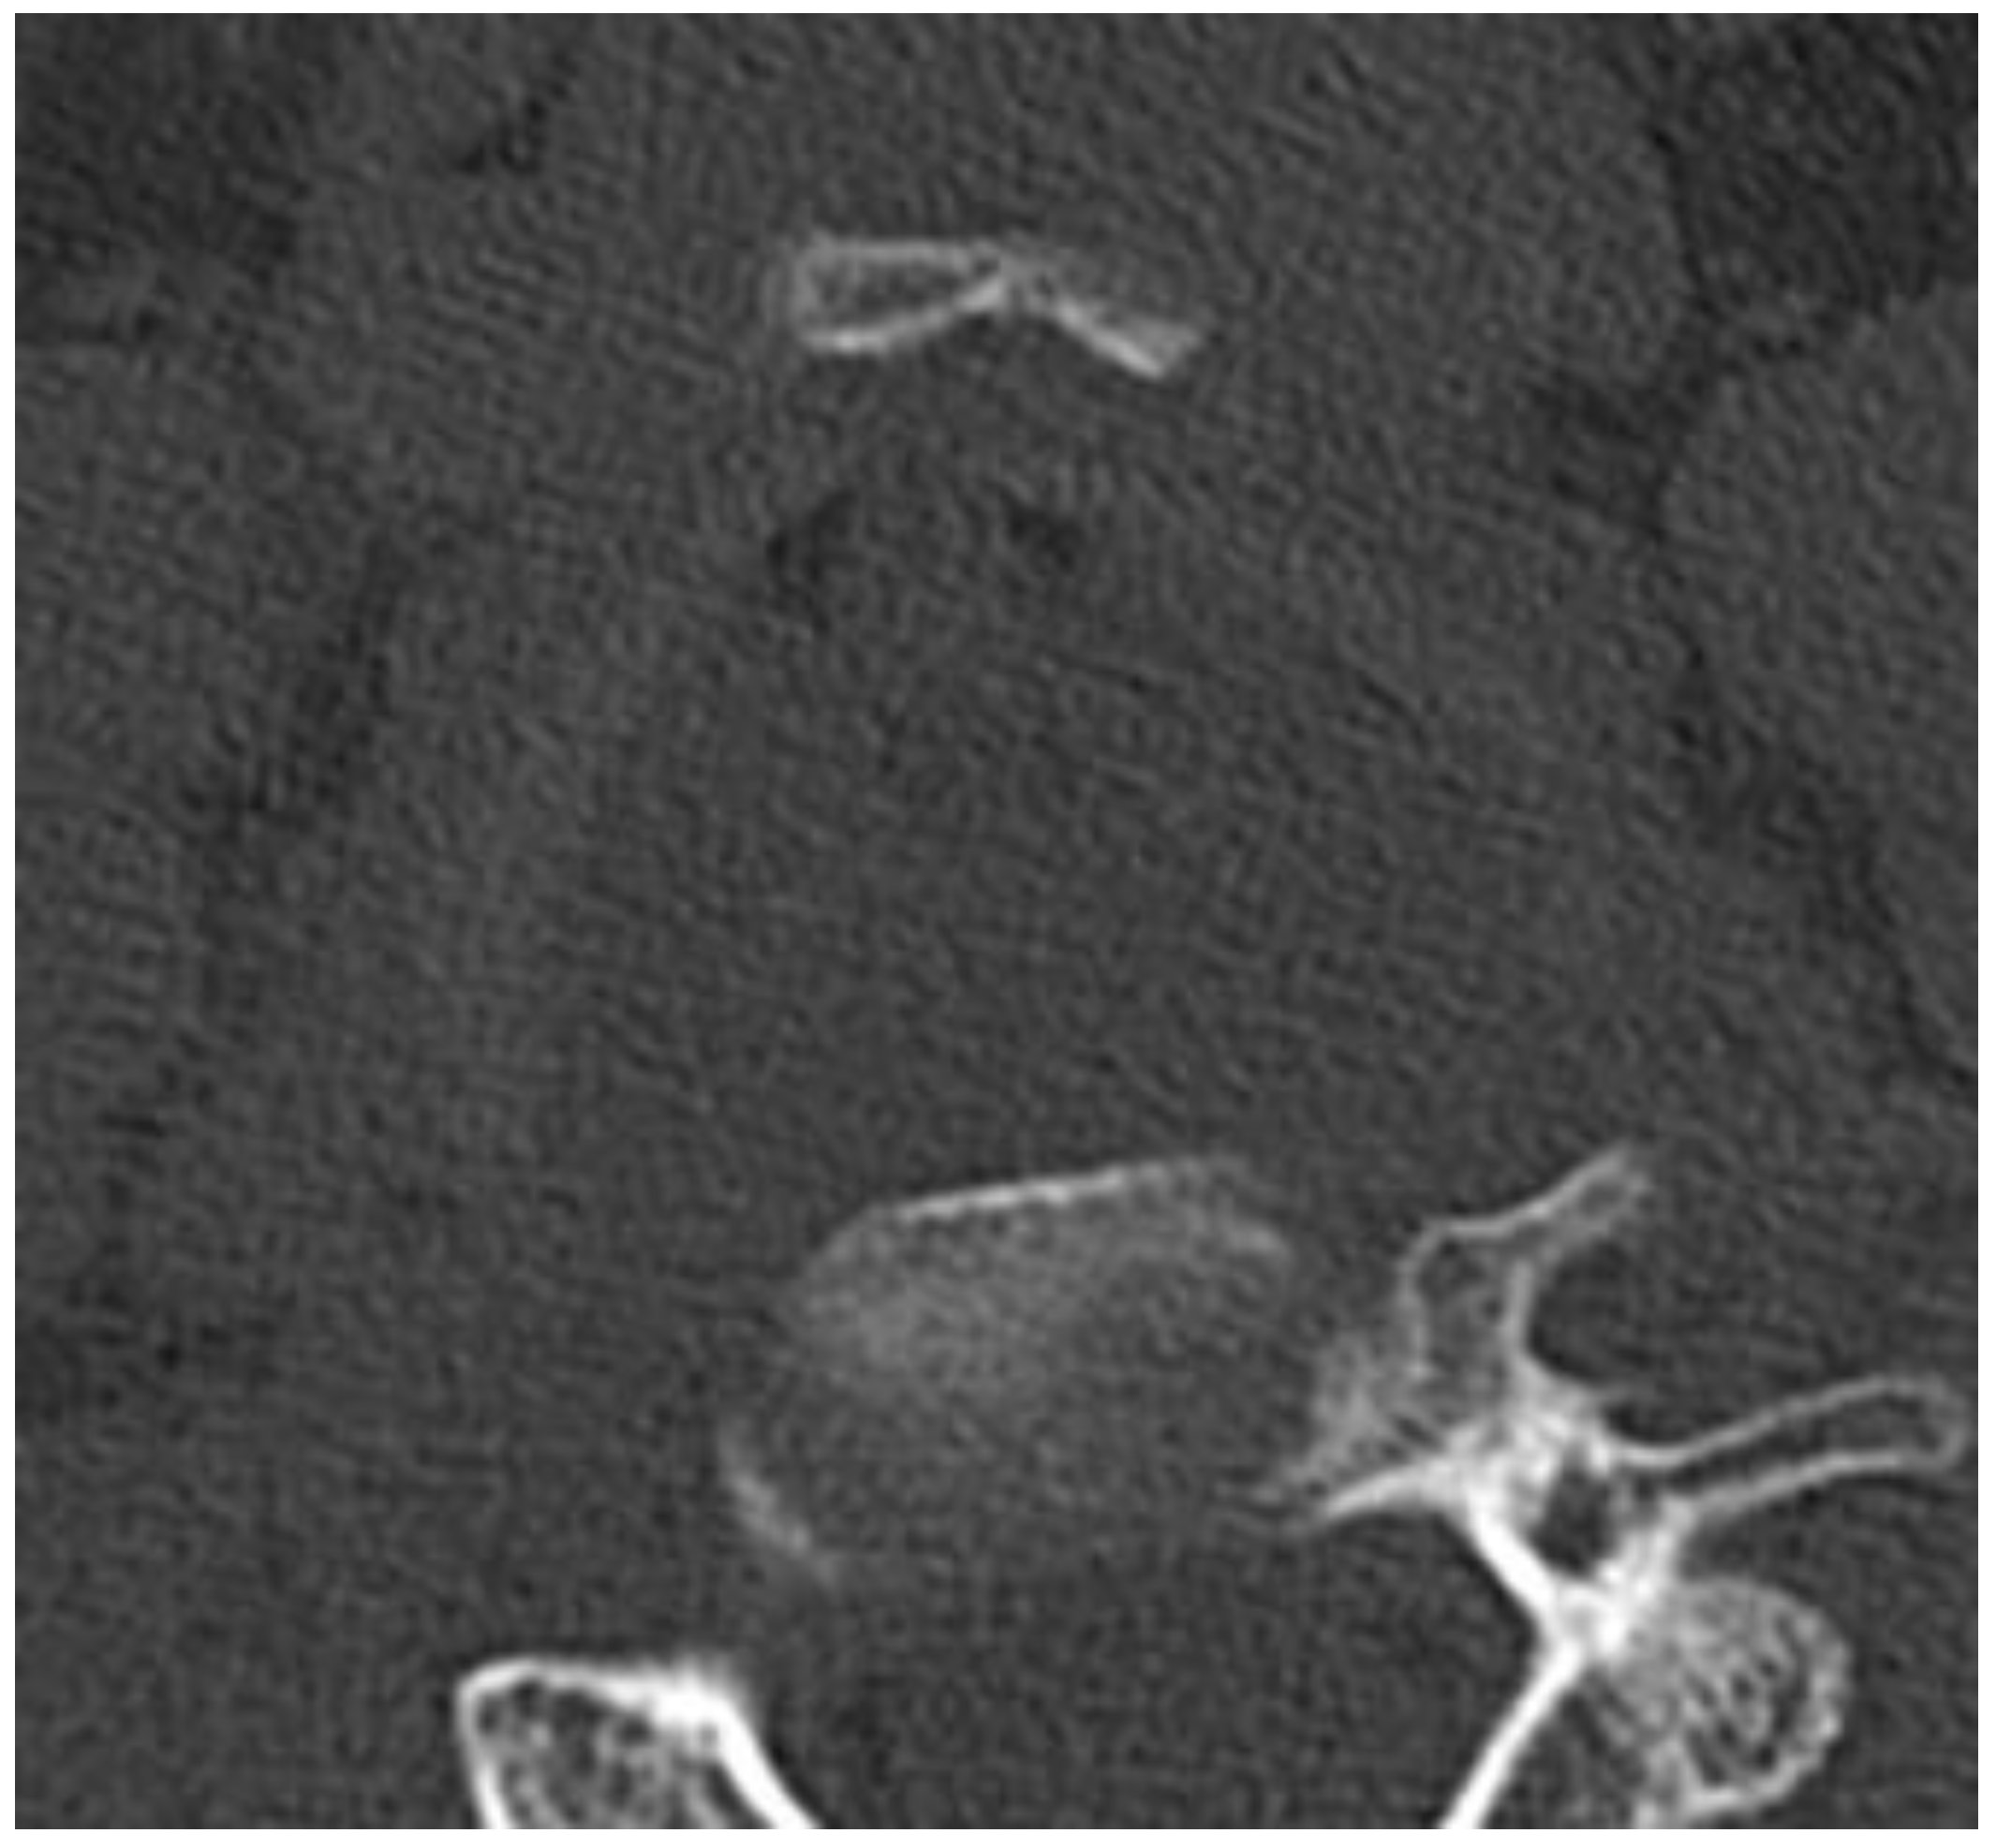

3.3. Evaluation of Specific Cases

3.4. Detailed Findings